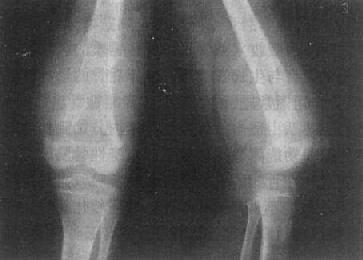

长骨巨细胞瘤的X线表现多较典型(图2-1-23),常侵犯骨端,症变直达骨性关节面下。多数为偏侧性破坏,边界清楚。瘤区X线表现可有两种类型,较多的病例破坏区内可有数量不等、比较纤细的骨嵴。X线上可见似有分隔成为大小不一的小房征,称为分房型。少数病例破坏区内无骨嵴,表现为单一的骨质破坏,称为溶骨型。病变局部骨骼常呈偏侧性膨大,骨皮质变薄,肿瘤明显膨胀时,周围只留一薄层骨性包壳。肿瘤内无钙化或骨化致密影,邻近无反应性骨膜增生。边缘亦无骨硬化带,如不并发骨折也不出现骨膜增生。破坏区骨性包壳不完整,并于周围软组织中出现肿块者表示肿瘤生长活跃。肿瘤边缘出现筛孔状和虫蚀状骨破坏,骨嵴残缺紊乱。侵犯软组织出现明确肿块者,则提示为恶性骨巨细胞瘤。肿瘤一般不穿破关节软骨,但偶可发生,甚至越过关节侵犯邻近骨骼。

图2-1-23 桡骨巨细胞瘤桡骨骨端边界清楚的骨破坏,

其中有多个骨隔将骨破坏区分成多个小房,病变有膨胀性